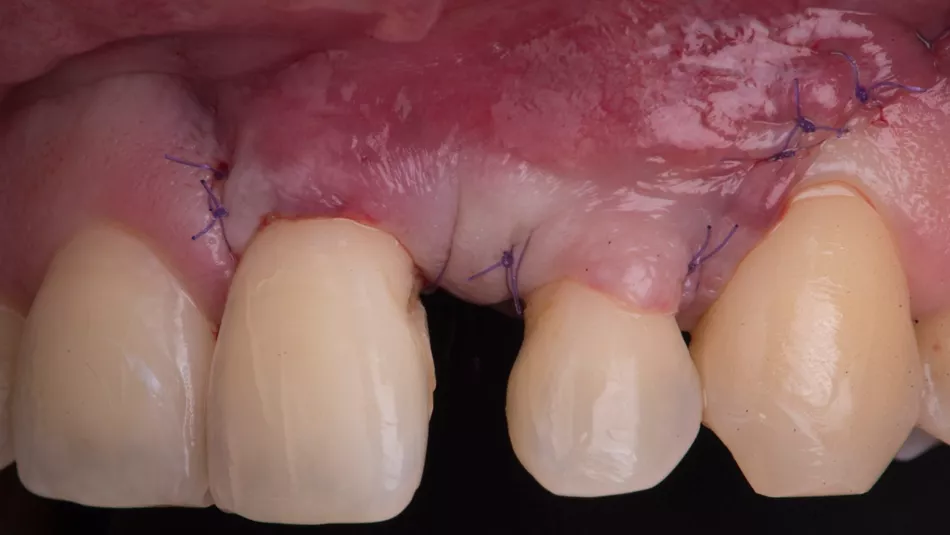

The flap was repositioned and sutured with an external vertical mattress suture and single interrupted loop sutures (Fig. 11).

Fig. 11

Control at 21 days post surgery (Fig. 12).

Fig. 12